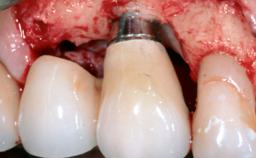

Surgical Treatment of Peri-Implantitis in the Posterior Mandible Associated with Hard- and Soft-Tissue Reconstruction

Paolo Casentini demonstrates that peri-implantitis can be successfully treated even at an advanced stage. He discusses a case in which the existing implants and prostheses were both retained while regenerating the defect and creating a band of keratinized tissue. A 69-year-old female patient was referred by her general dentist for evaluation of a recurrent infection at previously placed and restored implants in the posterior left mandible. The patient’s chief complaint was recurrent swelling and pain in the molar region of the left posterior mandible with discomfort during brushing in the same area. The patient reported receiving two implants (36 and 37) nine years earlier.